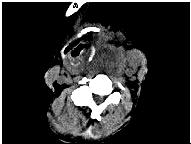

处理后: